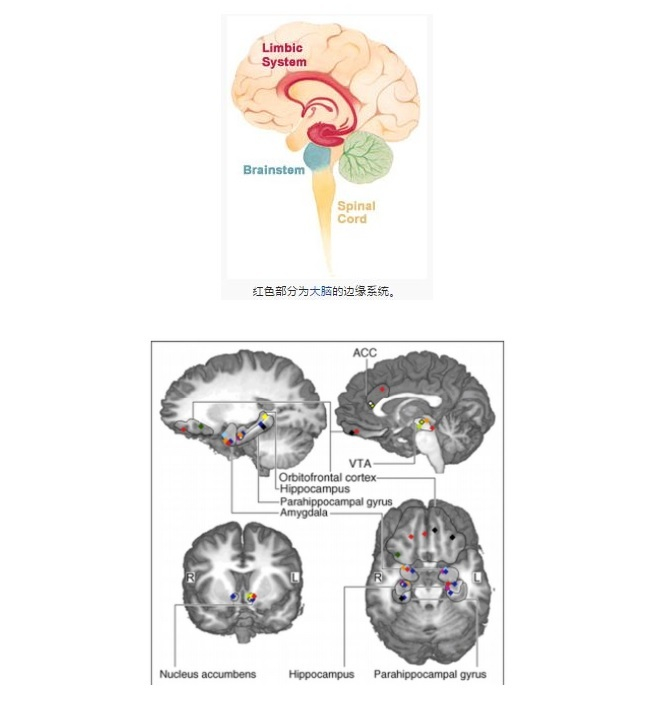

而技术学者们通过磁共振成像(MRI)等大脑成像技术监控脑部在音乐氛围中的活动,数据显示,人脑在听音乐的过程中不仅是影响了大脑中心区域,而是大脑几个部分会同时显示活动迹象——每个部分都会呈现复杂微妙的变化。